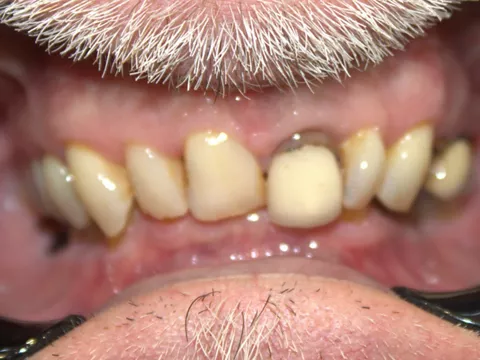

2a. 2b. Preoperative frontal and occlusal view of the lower arch showing multiple missing teeth.

2a

2b